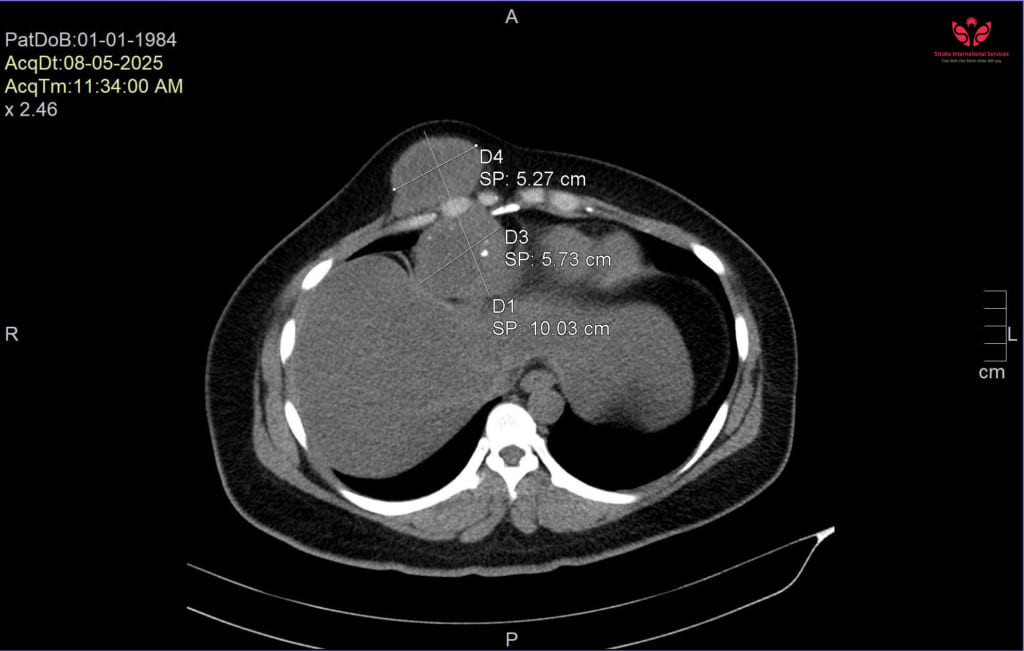

Qua thăm khám lâm sàng và cận lâm sàng, hình ảnh CT scan ghi nhận khối u có đường kính lên đến 11cm, trong đó một phần phát triển ra ngoài, một phần lan sâu vào trung thất, xâm lấn màng tim, màng phổi và xương sườn phải.